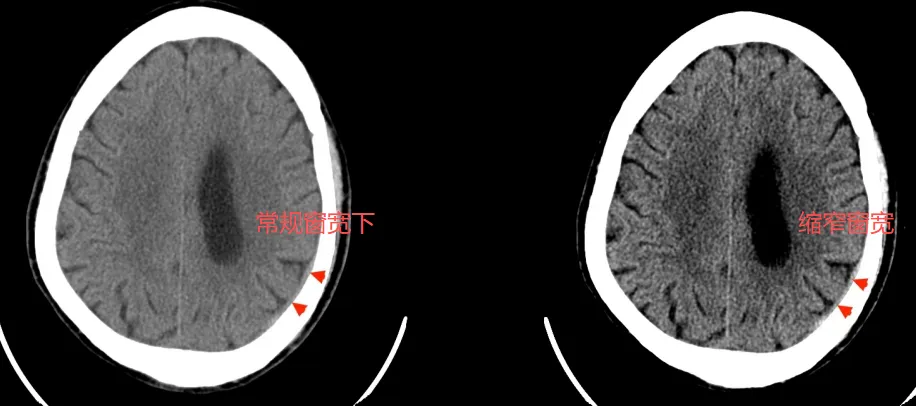

案例2:缩窄窗宽案例

第二种情况是:少量的血肿在颅脑不一定是高密度,而是和脑组织密度差不多,这个时候他们之间的对比度差别不大。为了能更好的显示病灶,这个时候应该是缩窄窗宽。